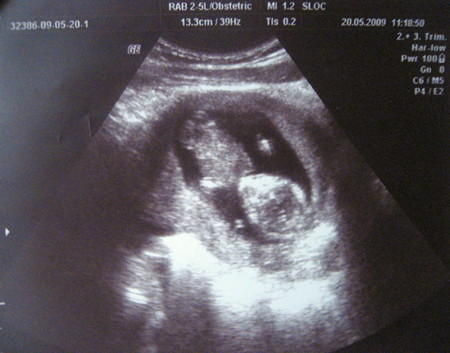

Екатерина 17 лет Первое УЗИ Сегодня 20 мая 2009 года первый раз сделала УЗИ.Срок 13 недель, врач сказал все хорошо Посмотрите еще 20 записей на эту тему Отменить Ответить Ирина Какие вы фотогигиеничные будущая модель 23.05.2009 Ответить Марина Рогожкина Поздравляю! Самое прекрасное время!!! Ожидание! 22.05.2009 Ответить Наська Класс))) Малюсенький человечек))) Удачный снимок. 22.05.2009 Ответить первый пинок....))) Чаты Беременных Выберите чат: Январята-2026 Февралята-2026 Мартята-2026 Апрелята-2026 Майчата-2026 Июнята-2026 Июлята-2026 Августята-2026